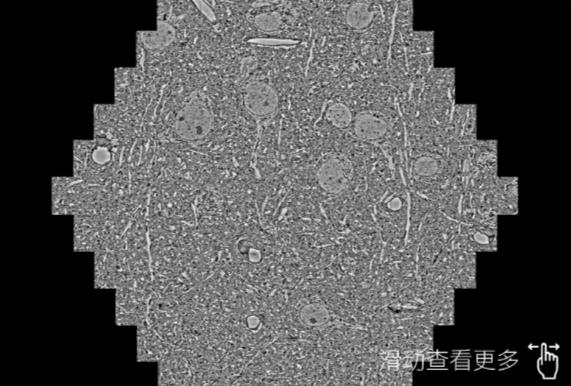

鼠脑切片。左图使用宿州蔡司宿州扫描电镜MultiSEM706对165μmx143pm面积区域成像,耗时仅需1.5秒。右图为鼠脑切片中30μm区域放大效果。样品由芝加哥大学B.Kasthuri提供。